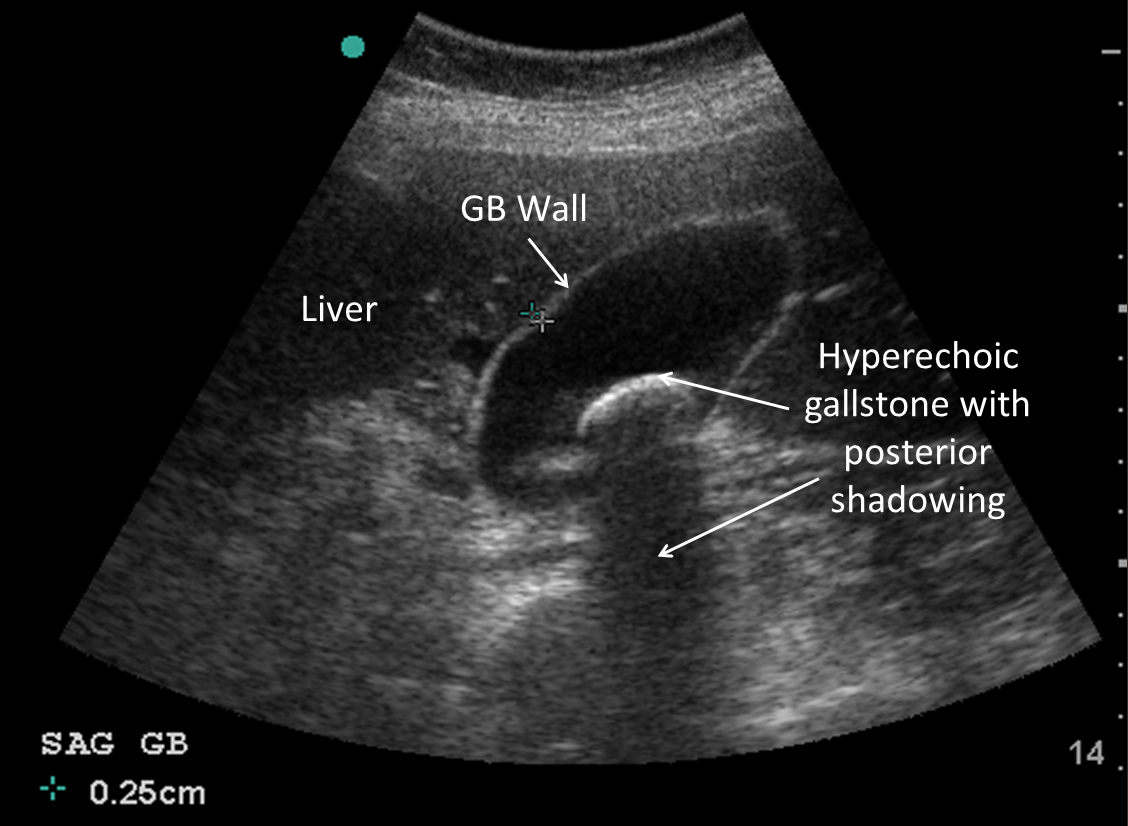

Biliary

Biliary pathology including cholelithiasis causing biliary colic and cholecystitis is a common finding in patients presenting to the emergency department with abdominal pain. Emergency ultrasound can hasten diagnosis and surgical consultation. The primary sonographic abnormalities noted in patients with biliary disease include the presence of gallstones, which are round, hyperechoic objects with posterior acoustic shadowing. Ultrasound criteria for cholecystitis include:

Gallbladder wall thickening >3mm

Pericholecystic fluid

Sonographic Murphy’s sign (Figure 24) (REF. 10)

Figure 24. Top image showing gallstones with characteristic shadowing artifact; bottom showing wall-thickening and pericholecystic fluid in cholecystitis (Images courtesy of Matthew Lohse, MD. Baylor Scott & White-Temple).